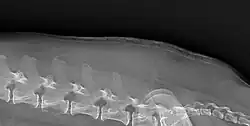

The symptoms of Cushing's in cats is similar to that of dogs.[8] For cats the most common reason for referral resulting in a diagnosis is diabetes mellitus. Abnormal dermatological findings were the most common reason for referral after physical examination in cats.[9] 80% of cats with Cushing's develop diabetes mellitus compared to 10% of dogs.[8] One study of cats found all 30 to have dermatological lesions, 87% to have polyuria or polydipsia, and 70% to have polyphagia.[9] Curling of the tips of the ears may occur.[2]

Cushing's may cause a breakdown of dermal proteins, causing shiny and thin skin, this can lead to secondary infection and is pathognomonic of Cushing's.[2]